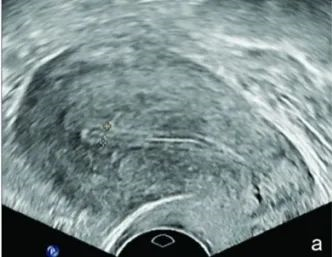

子宫内膜类型指内膜与肌层相对回声的状态。根据阴道B超检查子宫内膜的Gonen标准可以分为3种类型。

A型:典型三线型或多层子宫内膜;

B型:均一的中等强度回声,子宫腔强回声,总线断续不清;

C型:均质强回声,无子宫中线回声。

研究表明,hCG 注射日A型子宫内膜种植率和临床妊娠率显著高于B型和C型,提示A型子宫内膜为胚胎着床提供了更好的条件。A型子宫内膜和中度子宫内膜厚度最适于胚胎种植。